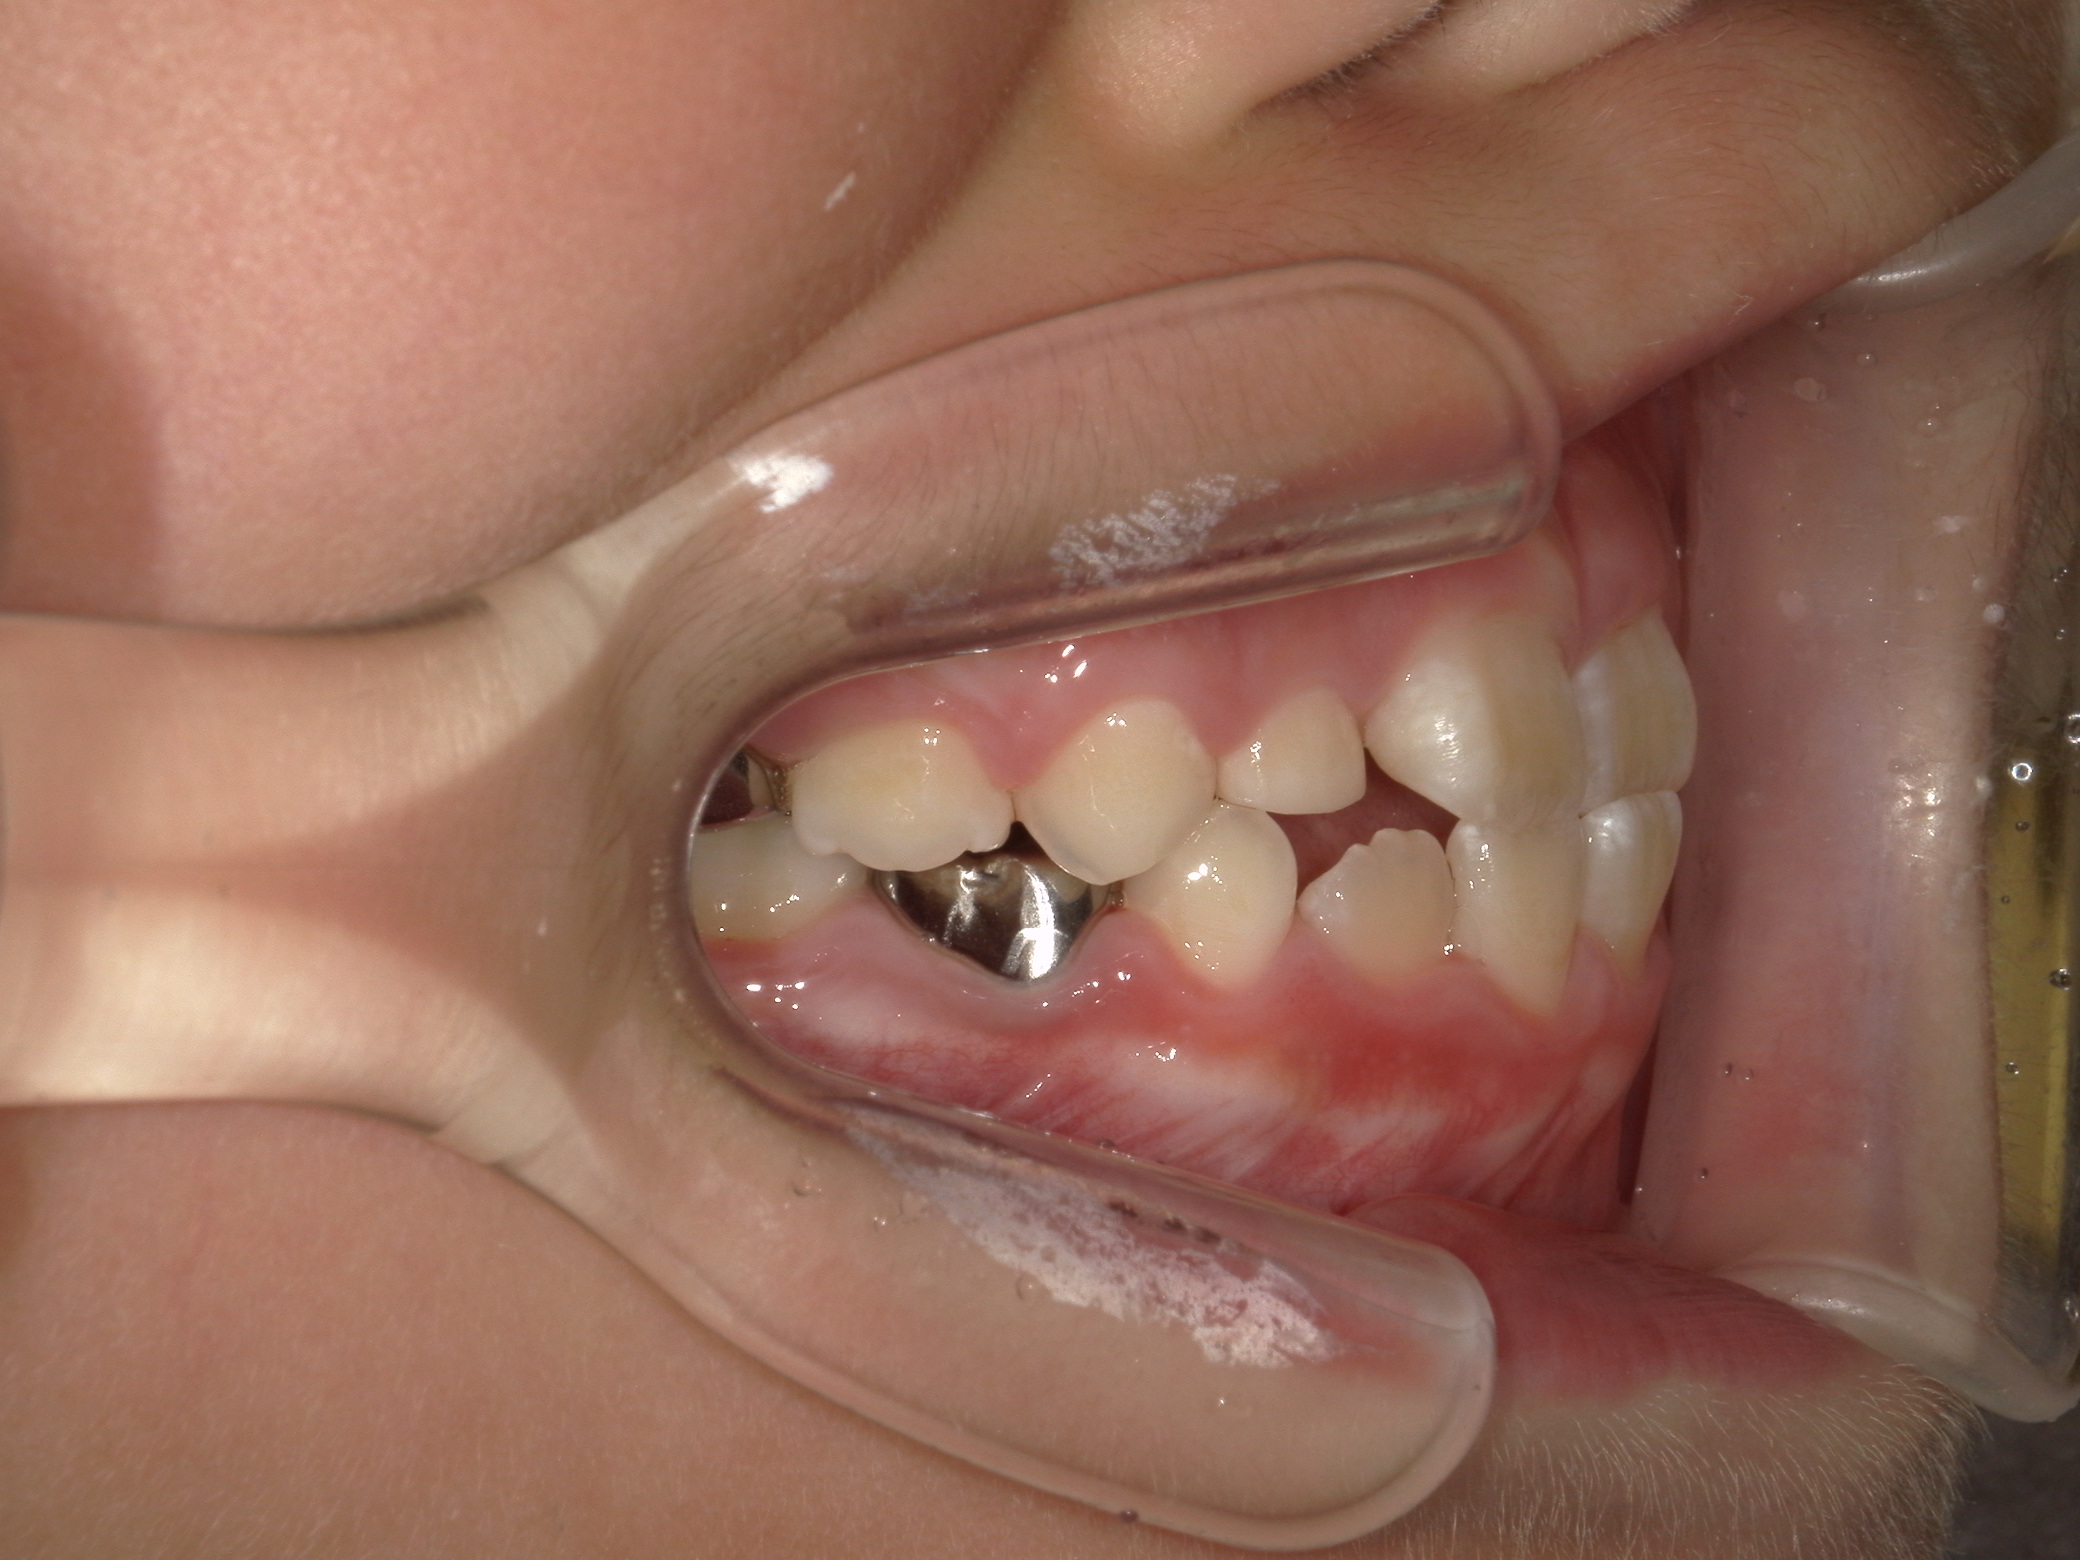

【小学生】マイオブレース矯正 反対咬合(受け口)を改善

小学生で開始

マイオブレース

受け口

非抜歯

1期治療のみで改善

Before

After

治療期間

1.6年

治療開始

8歳

種類

マイオブレース矯正

使用装置

機能矯正装置

コメント

装置装着と 筋機能療法をきっちり取り組んでくれましたので

スムーズに治りました。

現在も安定して 後戻りしていません。